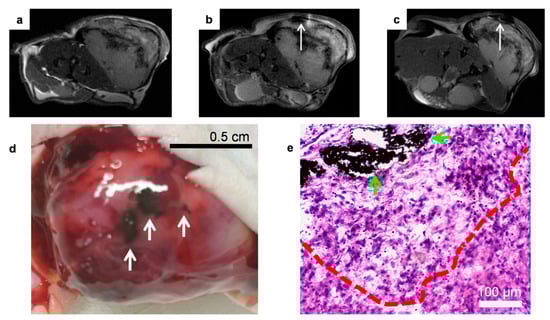

3.6. In Vivo Imaging-Guided TP-Photothermal Therapy